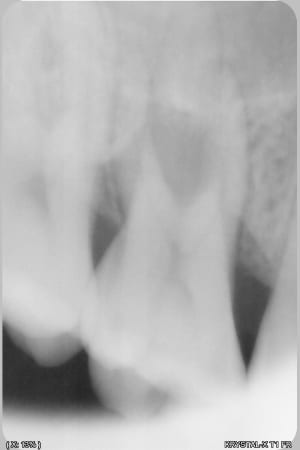

559940449_10163144646462247_7720006236309727129_n.jpg